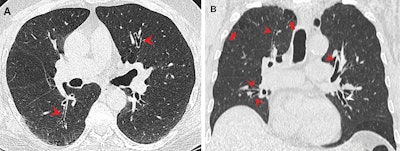

CT images show airway changes in a 66-year-old male marijuana and tobacco smoker with cylindrical bronchiectasis and bronchial wall thickening (arrowheads) in multiple lung lobes in a background of paraseptal and centrilobular emphysema. Image and caption courtesy of the RSNA.

The researchers found that the proportion of patients with paraseptal emphysema is higher in the cigarette smoker and combined smoker groups. They also found that marijuana smoking was tied to a five- to seven-times higher risk of developing paraseptal emphysema than nonsmokers.

Additionally, the researchers found that the combined smoking group was 12 times more likely to have centrilobular emphysema than nonsmokers. This is a type of pulmonary emphysema where the air sacs within the lungs are damaged, leading to breathing difficulties and other serious respiratory symptoms.

Finally, the team reported that the combined smoker group had a four times higher risk of developing bronchial wall thickening than nonsmokers. However, it also found no significant association between marijuana smokers and gynecomastia.